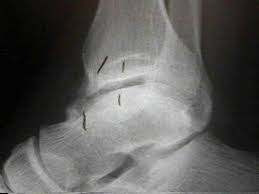

Stress fractures of the medial malleolus in the professional soccer player demonstrate excellent outcomes when treated with open reduction internal fixation and arthroscopic spur debridement anthony nguyenian beasleyjames calder knee surgery, sports traumatology, arthroscopy. Case contributed by dr henry knipe ◉ ◈. Medial malleolus and talus make up the medial side. The medial malleolus is the prominence on the inner side of the ankle, formed by the lower end of the tibia. What is the largest tendon of the calcaneus?

The doctor check the xray and told me that the bones are not totally joined yet and it will take more 15 days. Malleolus fractures leading to over treatment. Surgery on the medial malleoli can improve the chances of successful healing and allow the person to resume normal movement sooner. These also link to further pages about related topics such as specific types of fractures, bone diseases and. In anatomical position the palms are facing up, making the ulna the medial bone of the forearm.